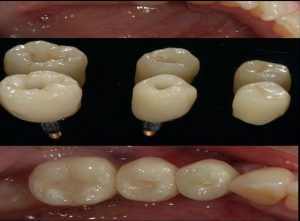

Implant, Crown

Implant, Bridge, Crown

Implants